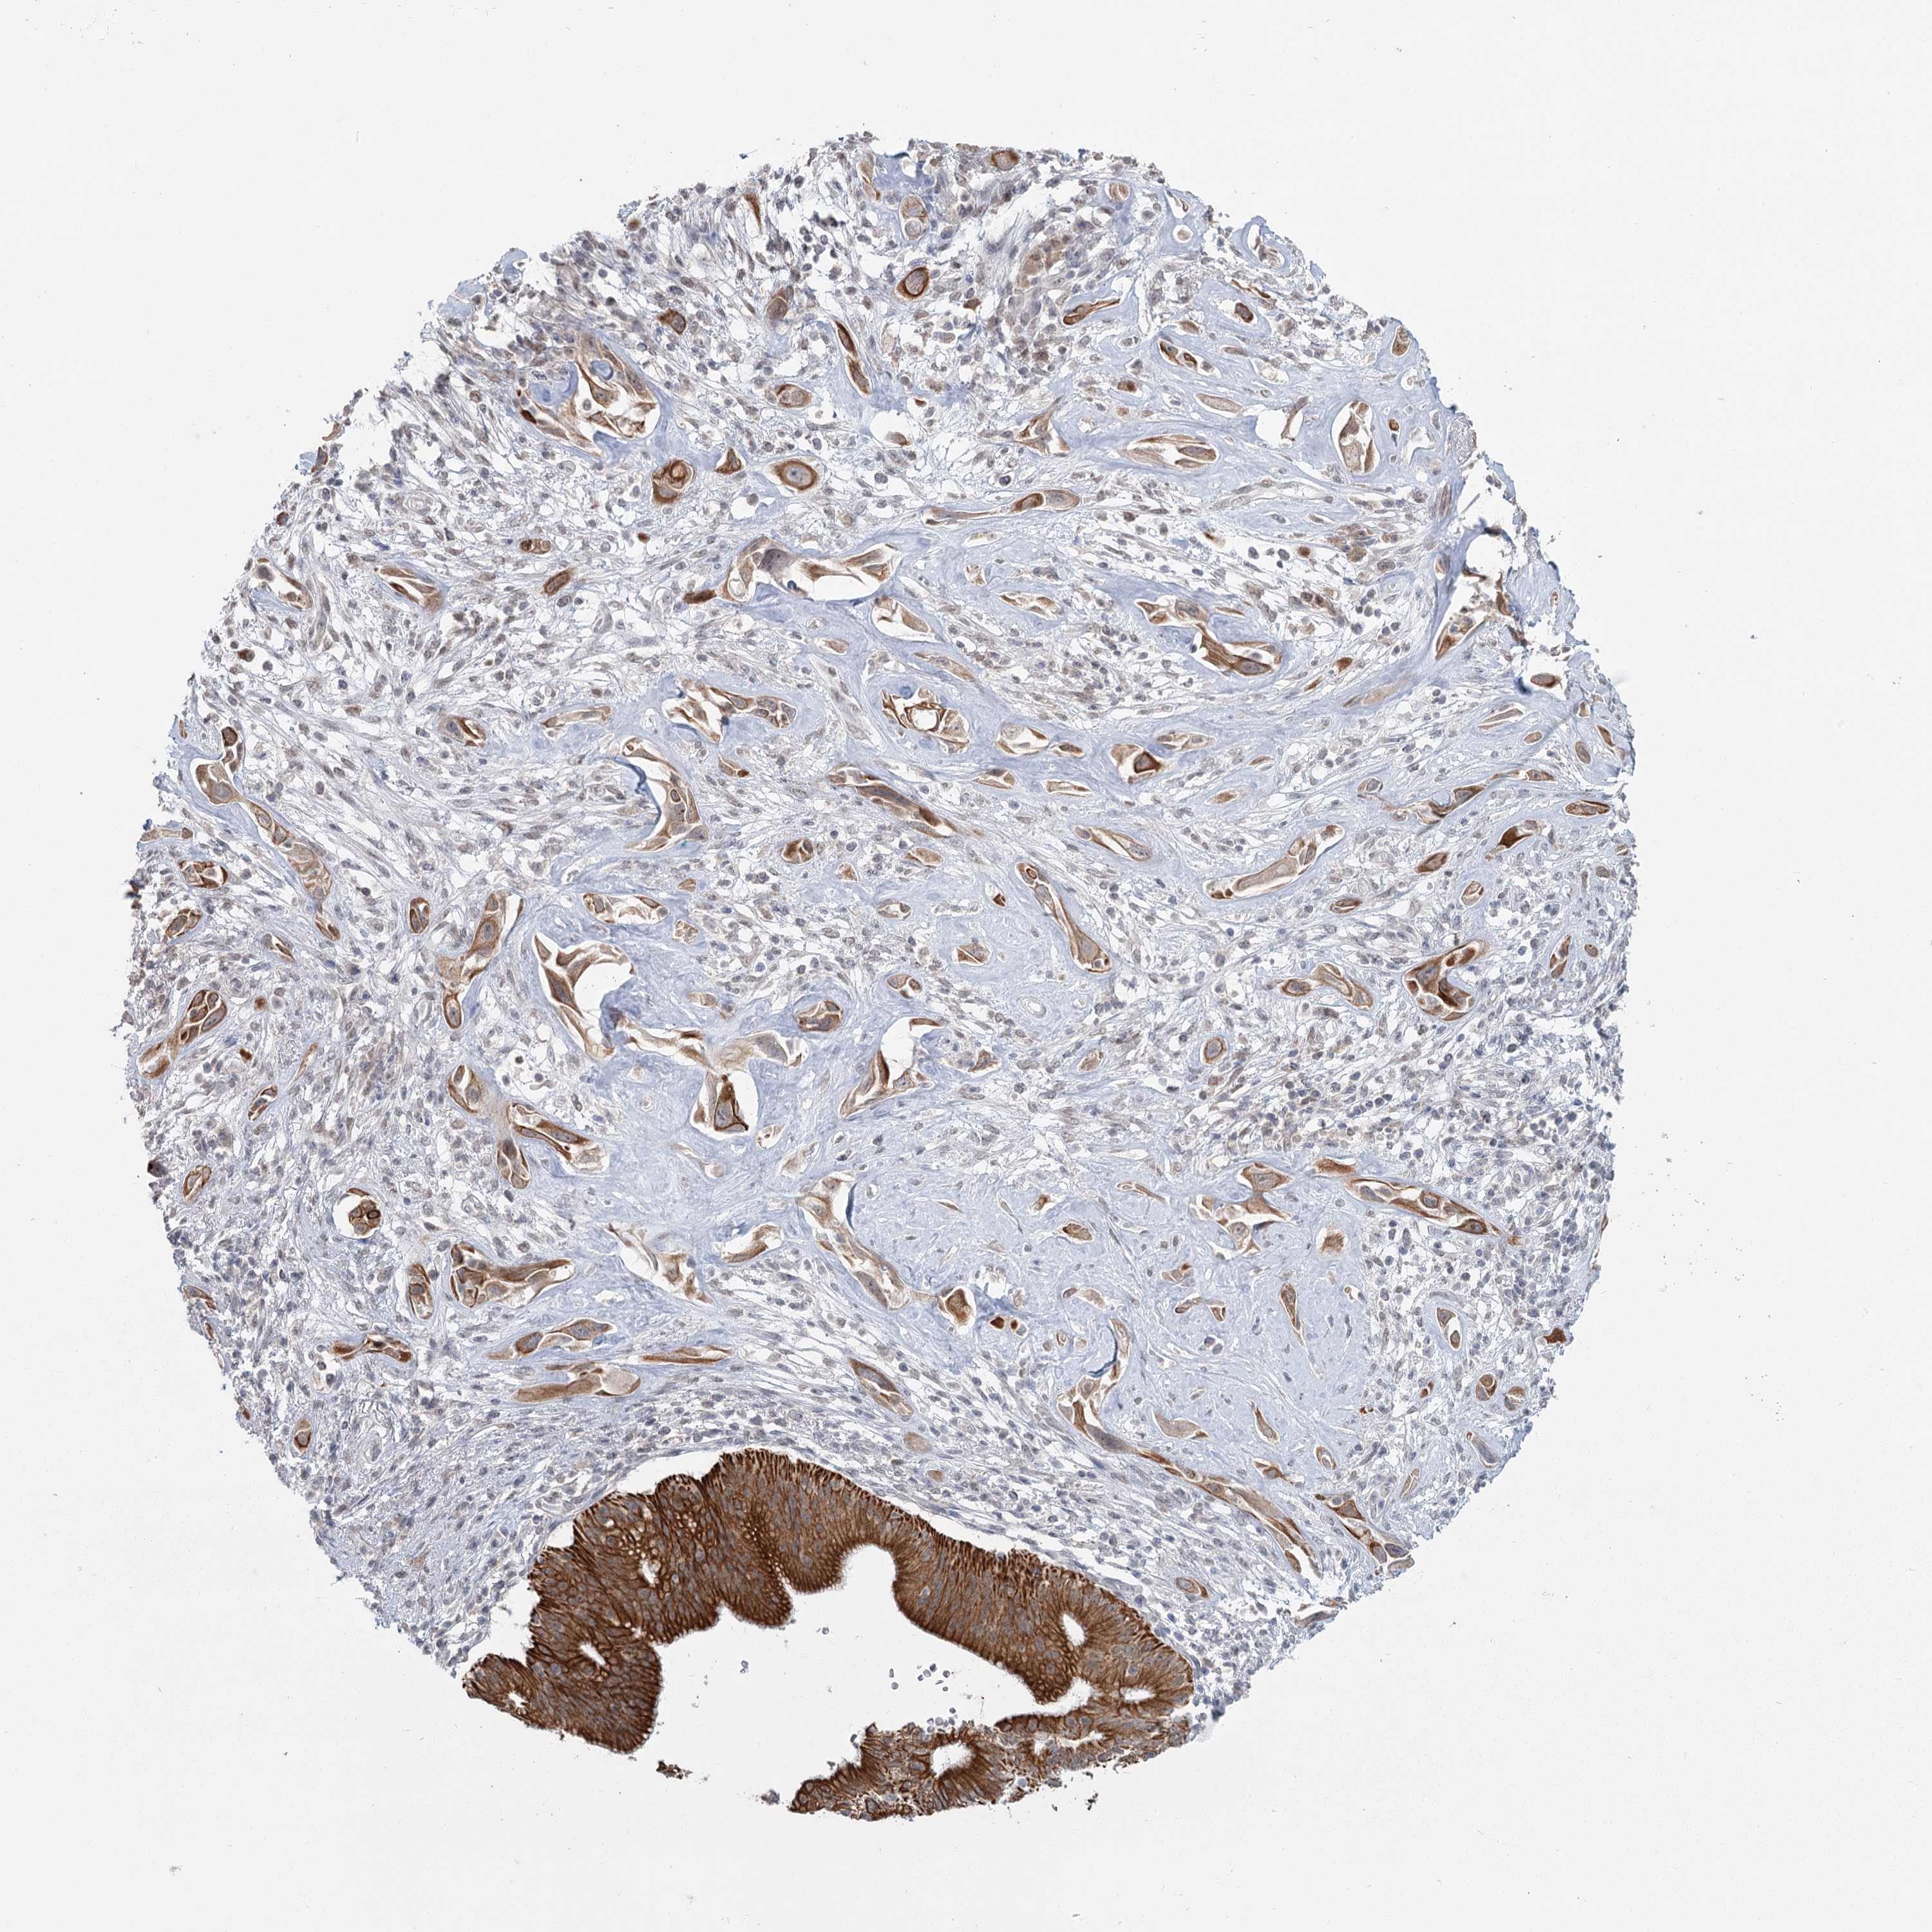

PANCREATIC CANCER - Protein expressioni

A mouse-over function shows sample information and annotation data. Click on an image to view it in a full screen mode. Samples can be filtered based on level of antibody staining by selecting one or several of the following categories: high, medium, low and not detected. The assay and annotation is described here.

Note that samples used for immunohistochemistry by the Human Protein Atlas do not correspond to samples in the TCGA dataset.

Antibody stainingi

Antibody staining in the annotated cell types in the current human tissue is reported as not detected, low, medium, or high, based on conventional immunohistochemistry profiling in selected tissues. This score is based on the combination of the staining intensity and fraction of stained cells.

Each image is clickable and will lead to virtual microscopy that enables deeper exploration of all samples and also displays staining intensity scores, fraction scores and subcellular localization as well as patient and tissue information for each sample.

Antibody HPA023187

Antibody CAB034226

Staining

High

Medium

Low

Not detected

Adenocarcinoma, NOS